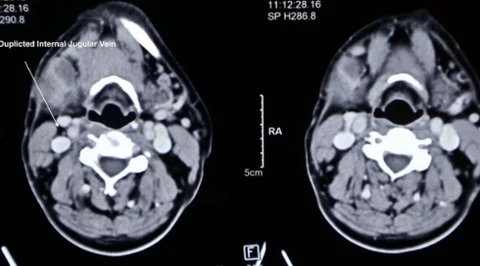

Nietypowe odkrycie podczas operacji szyi - w historii odnotowano cztery takie przypadki

Niezwykłe odkrycie podczas operacji szyi. To dopiero piąty taki przypadek